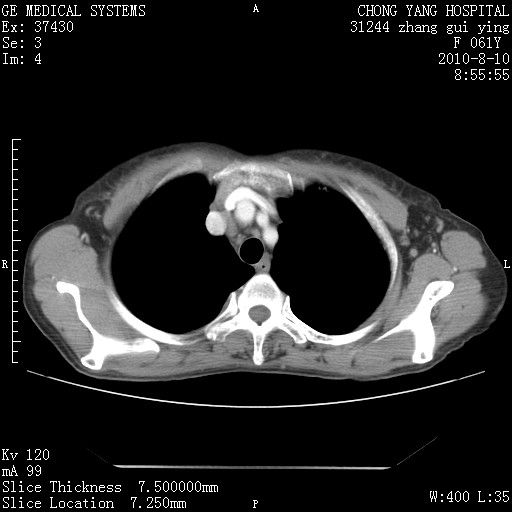

标题: CT28314:F61Y胸部增强,发热咳嗽一周入院,后面的为一周前平 [打印本页]

标题: CT28314:F61Y胸部增强,发热咳嗽一周入院,后面的为一周前平

1、支持考虑右侧中央型肺癌伴右肺中叶节段性不张及下叶支气管黏液痰栓    2、左肺上叶舌段感染。

支持3楼意见,还要考虑:纵隔及肺门淋巴结转移、右侧少量胸腔积液。

确切的说:1:右肺下叶中心型肺癌侵及中叶支气管并中叶不张,纵膈淋巴结转移。2:左肺舌叶炎症。3:右侧胸腔少量积液

块影平扫32hu,动静脉期62-70hu.